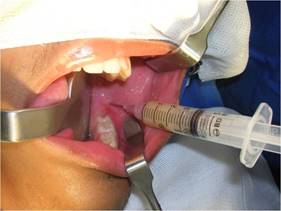

Nasotracheal intubation was done under general anesthesia after extra and intraoral antisepsis with 2 and 0.12% chlorhexidine. The operative field was placed, and the oropharynx cross-section was packed. Subperiosteal infiltration was performed at the retromolar trigone region-where there was cortical erosion due to fluctuation-with 0.5% bupivacaine hydrochloride solution with 1:200,000 epinephrine hemitartrate to promote hydrodissection of the periosteum and hemostasis. Next, aspiration was performed with a 10 cm³ Luer syringe with a 40X12 needle, and abundant seropurulent liquid was collected (Fig. 3).